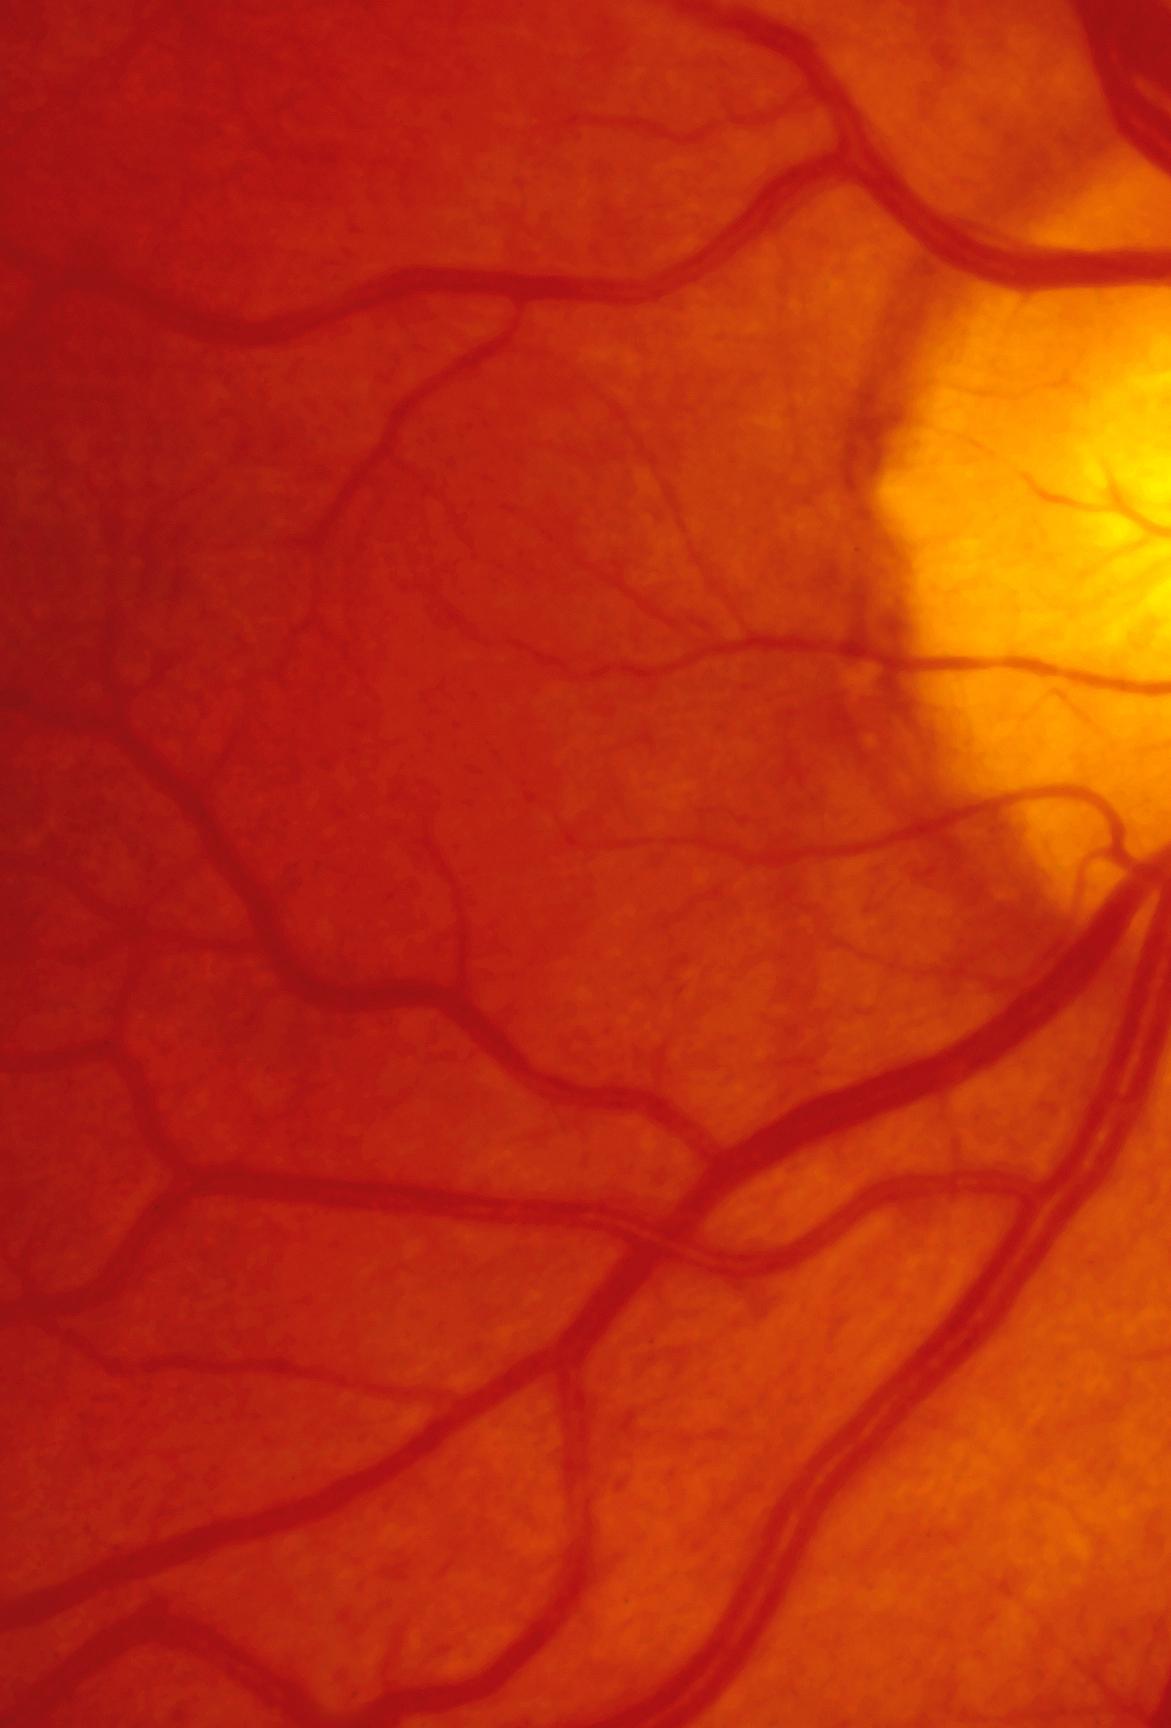

Estudio PET con 6-[18F]DOPA 3A) y [18F]OCTREOTIDE 3B) en cortes coronales de secuencias T2 de miembros pélvicos y con imágenes fusionadas, donde se identifica mayor sobreexpresión anormal de los receptores de somatostatina al compararlos con 6-[18F]DOPA, y que hace candidata a la paciente para PRRT.